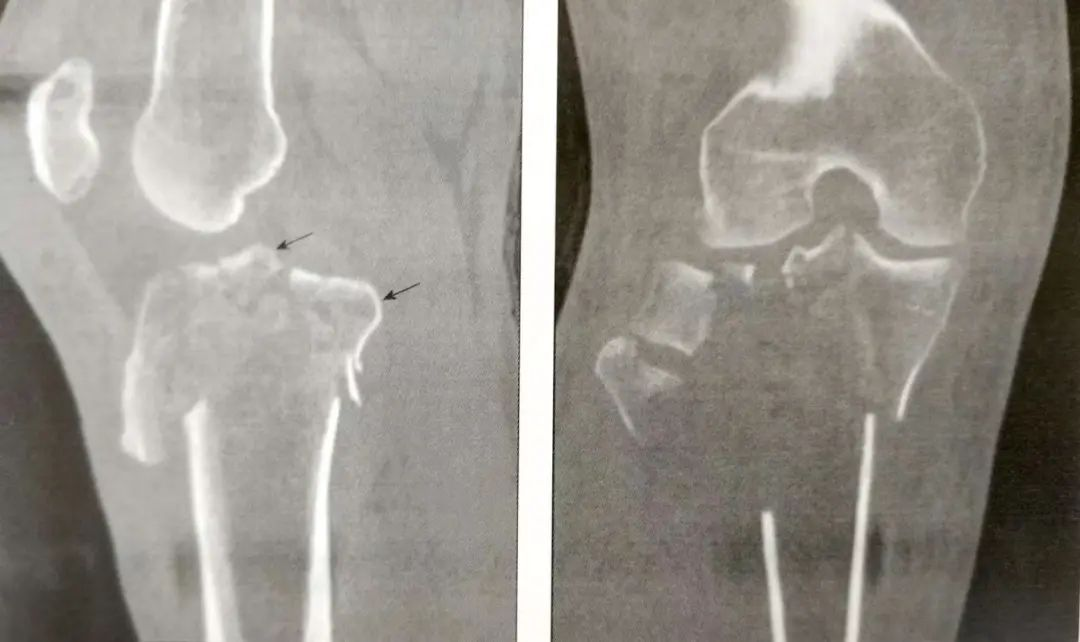

A:正位片;B:侧位片

CT扫描能有效观察关节内骨折情况。标准的扫描应该包括轴位、冠状位和矢状位;

CT可以提供完整的关节损伤信息,包括髁间嵴骨折,关节面塌陷的位置和程度,骨折块的大小,前交叉韧带撕脱骨折和后交叉韧带胫骨附着点撕脱骨折。

A:前交叉韧带撕脱骨折(箭头)

B:后交叉韧带胫骨附着点撕脱骨折

它们帮助确定骨折的切口。如一个前外侧髁间嵴骨折,需要采用膝关节外侧入路。

▲前外侧髁间嵴骨折(箭头)